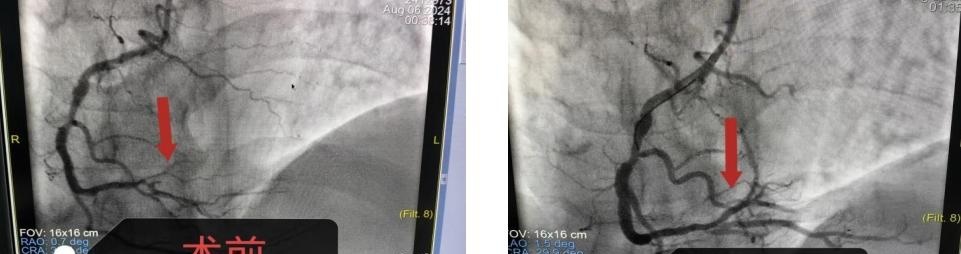

入院后立即予以完善心电图,显示ST段抬高心肌梗死。完善抽血检查后考虑急性心肌梗死超急性期。心血管内科二区副主任李贺跟家属充分沟通后,予以完成冠脉造影,造影结果显示:左前降支狭窄90%,左回旋支狭窄95%,右冠近端狭窄70%远端闭塞。属于冠心病中较严重的三支病变。

考虑到患者年轻对金属支架比较抗拒,副主任李贺手术团队火速为其制定专属治疗方案——予以行药物球囊扩展术。